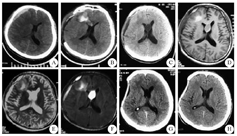

患者男,48岁,因被高空坠物砸伤头部于2014年2月24日在陕西神木县人民医院神经外科治疗。入院时处于昏迷状态,头颅CT检查显示"脑挫裂伤,右侧急性硬膜下血肿",行开颅血肿清除术并去骨瓣减压术。术后CT复查显示脑内血肿增多,深部累及胼胝体膝部,占位效应不重,继续给予输液治疗,症状逐渐好转,神志转清。约20 d后复查CT见类圆形透明隔囊肿,呈张力性扩张,囊液密度高于脑脊液。MRI检查显示囊液信号与慢性硬膜下血肿相似,脑室系统无明显扩大。患者无相关临床症状,未行特殊处理。出院时神志清楚,肢体活动大致正常。2个月后来肥城市人民医院脑外科复诊,行头颅CT检查显示囊肿消失,但残留透明隔间腔,患者无自觉症状。患者典型影像学资料具体见图1。

A:入院时CT显示硬膜下血肿,透明隔正常;B:入院第5天CT显示迟发性脑内血肿,深部累及胼胝体膝部,透明隔正常;C:入院第21天CT显示透明隔张力性囊肿;D~F:入院第21天MRI显示囊液T1像等信号,T2像及FLAIR像高信号;G:出院后2个月CT显示囊肿缩小,囊液密度与脑脊液密度相同;H:出院后4个月CT显示透明隔间腔仍存在